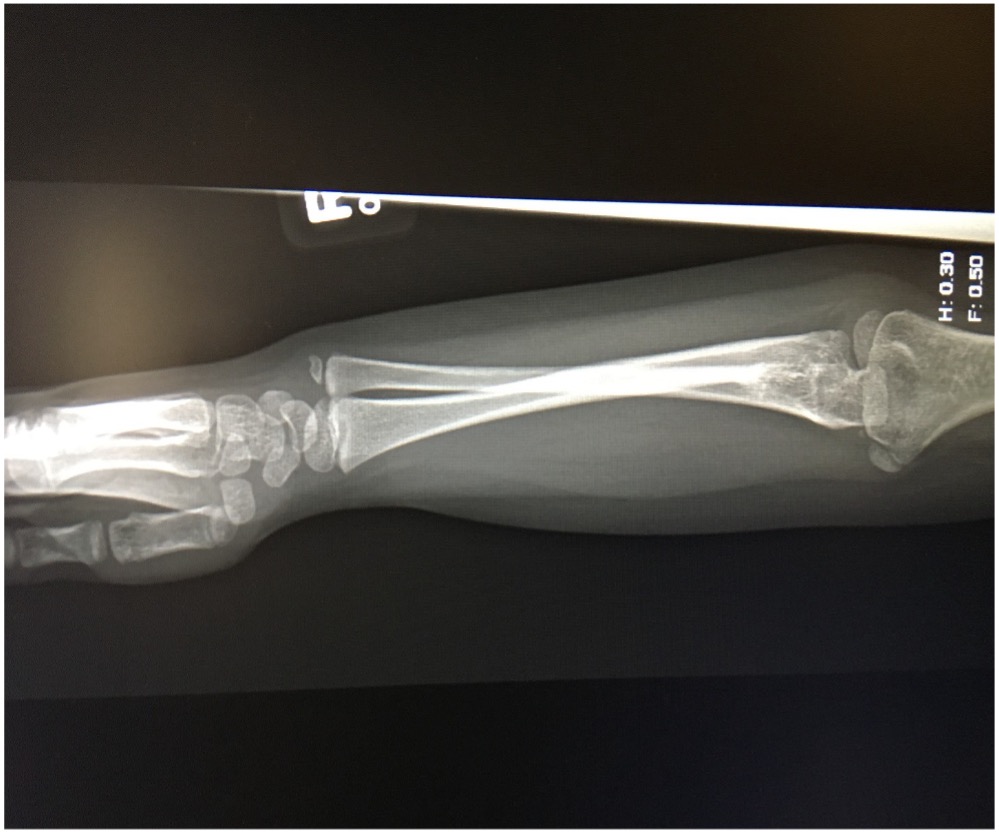

Some mild tenderness was noted upon deep palpation of the lateral elbow. The patient also had clinodactyly of the fifth phalange bilaterally. No other skeletal abnormalities were noted. A 3-view radiography scan of the elbow was conducted, results of which showed bilateral radioulnar synostosis (Figures 1-4). No wrist abnormalities were identified.

Figure 3. A radiology scan of the patient’s upper right extremity, lateral view.

Figure 4. A radiology scan of the patient’s upper right extremity, medial view.

CRUS has been described based on radiological classifications, the anatomical location of synostosis, and how it influences functionality. The most common radiological classification of CRUS, described by Cleary and Omer, is based on the appearance of the synostosis and reduction of the radial head (Table).6,10 Type I occurs with no osseous synostosis but a reduced radial head. Type II occurs with bony synostosis. Type III occurs with osseous synostosis with a hypoplastic and posteriorly dislocated radial head. Type IV occurs with short osseous synostosis with an anteriorly dislocated radial head. The radiological findings in our patient depicts a type II congenital radioulnar synostosis (Figure 1). Another description was explained by Wilkie, for which type I shows a connection between the radius and ulna occurs at the medullary canal; with type II, the fusion occurs distal to the proximal radial epiphysis and the radial head is dislocated anteriorly or posteriorly.4 A third description, which pertains to just the proximal radioulnar synostosis has also been portrayed.11 In type I, there is an absence of the radial head followed by complete radioulnar synostosis. In type II, the proximal part of the radial head is present but often deformed, and fusion occurs at the neck of the ulna. In type III, the head of the radius is always deformed and subluxed with synostosis occurring at the proximal area of the interosseous bones.